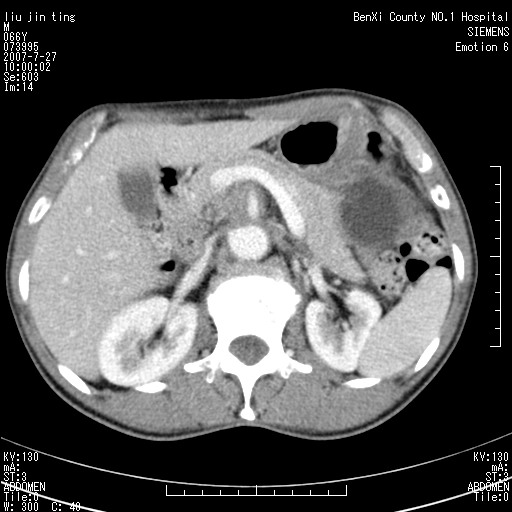

腹痛,背痛,无恶心呕吐,不黄,彩超示胰腺钩癌,ct扫描病灶平扫30-40hu,增强后动脉期40--60hu,静脉期50-68hu,真的是钩突上的么?您要试一试么?

动脉期

静脉期